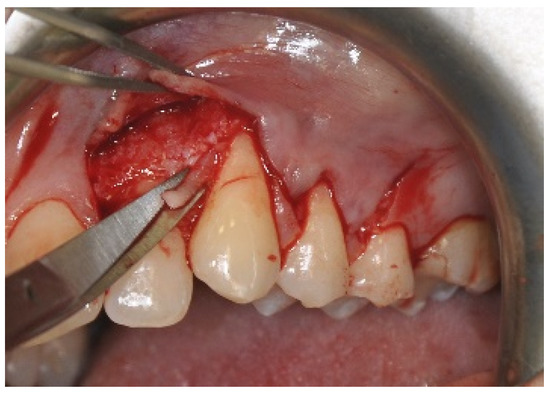

2.3. Surgical Procedures

Surgical Procedure Using Biokol®, the Xenogeneic Lyophilized Collagen Sponge